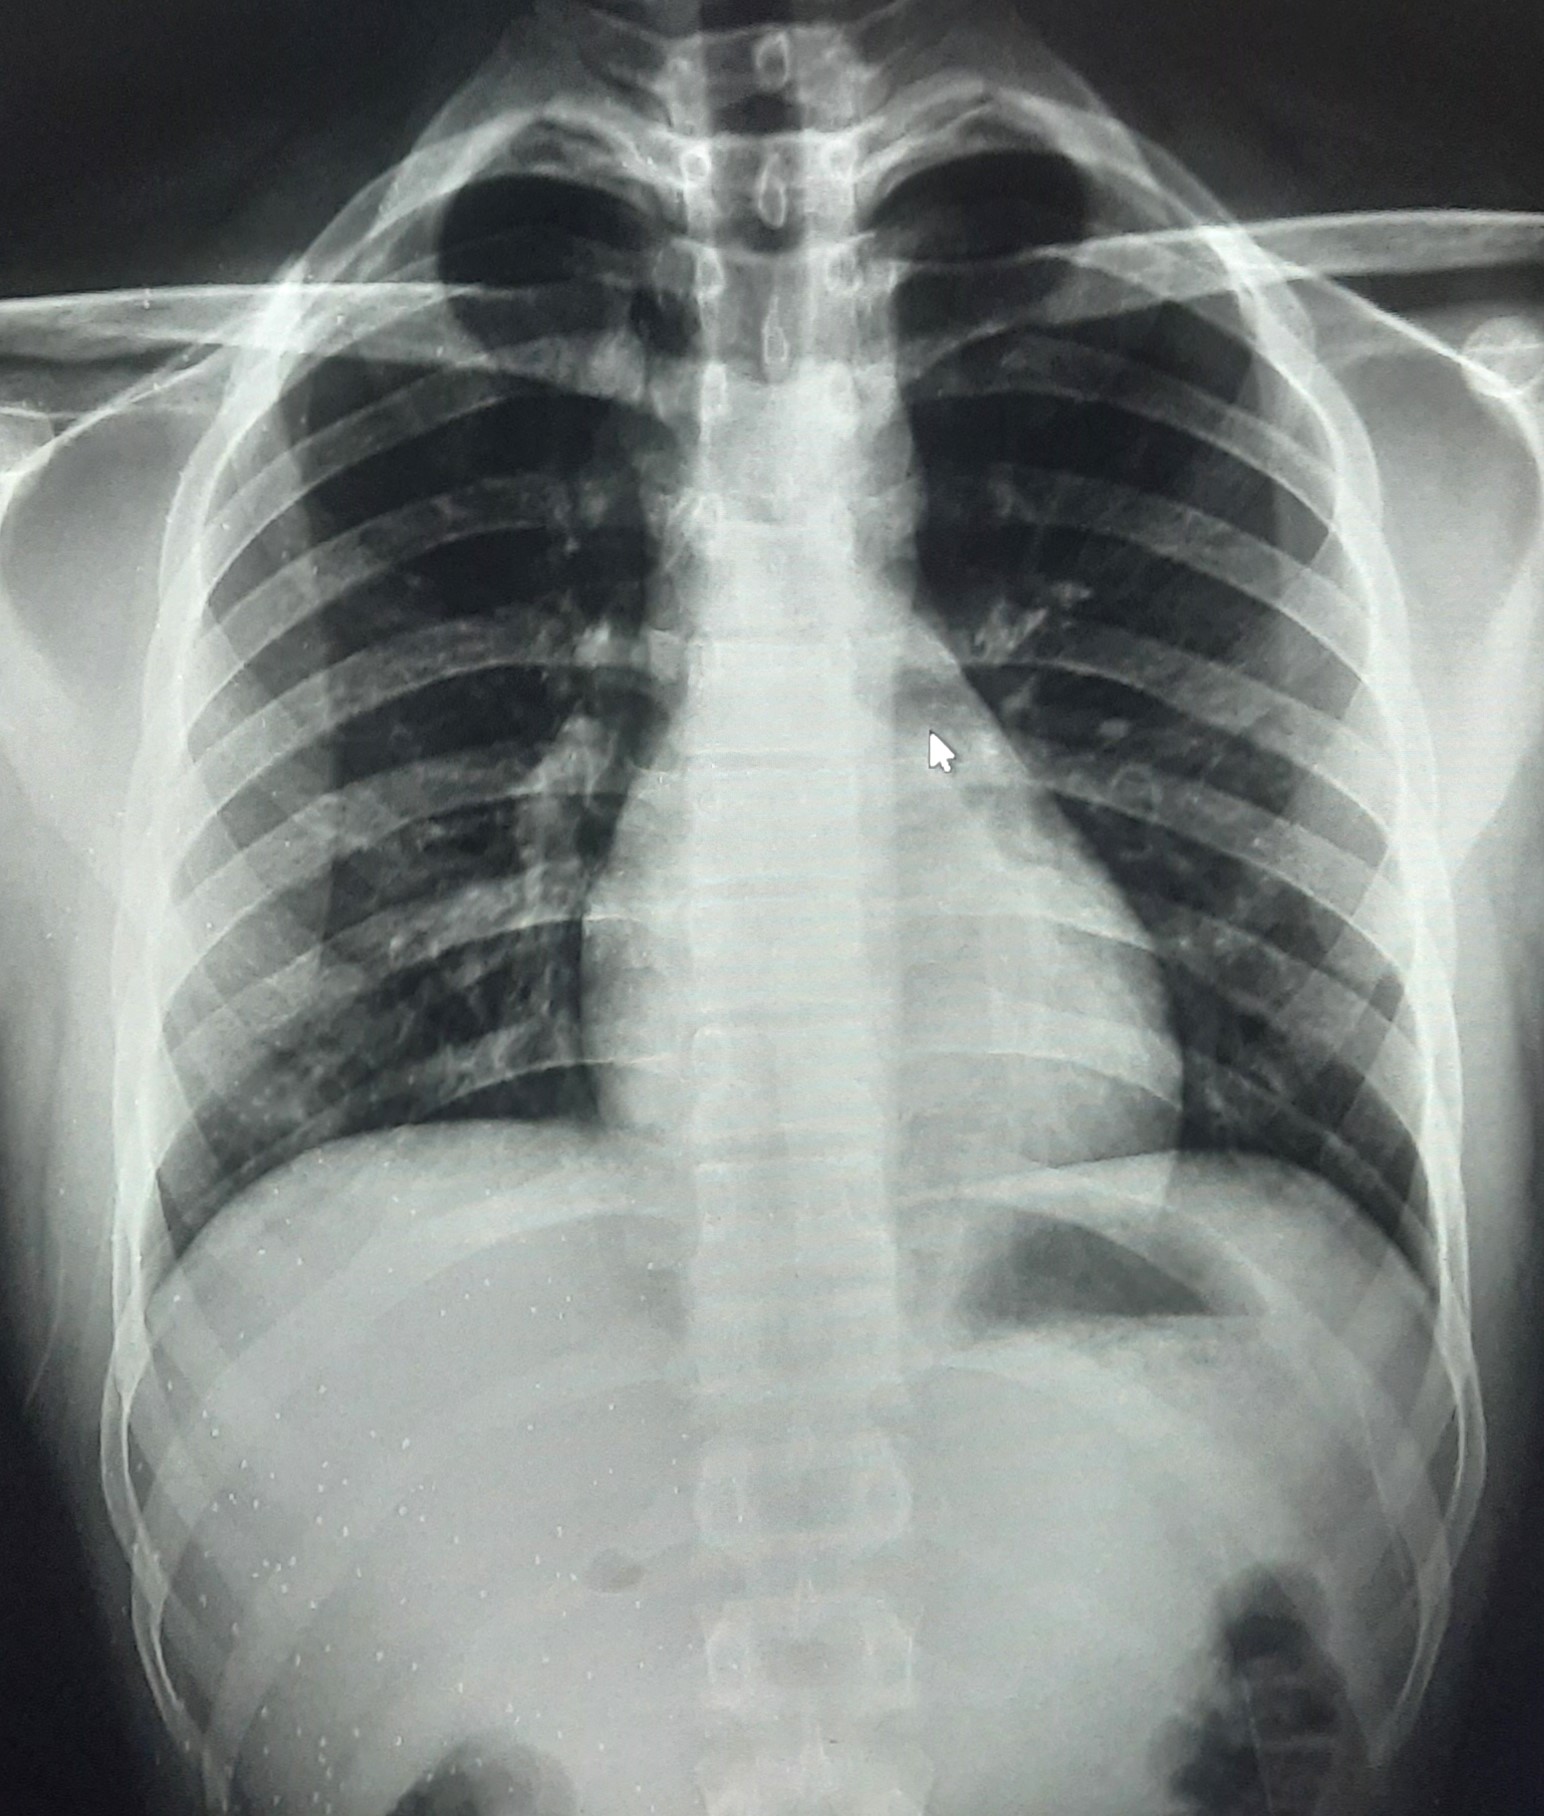

| 283 | IGGMC, Nagpur, Nagpur | P2 | 29-4189 Follow-up of 29-3923 |

Monali Pralhad Milmile | Consent taken on Paper | 46 Yrs. |

Provisional Diag : PTB Follow-up

Final Diag : Pleural Effusion |

TB Case (Confirmed) | Right Sided Upper Zone Fibrotic Lesion, Tracheal Pull Left side, Right sided & Left Sided Pleural Thickening Present, Right sided & Left Sided CP Angle Blunting Present, | Abnormality visible on x-ray |